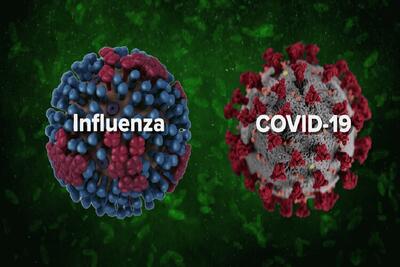

شیوع آنفلوانزا در یاسوج - تسنیم

استاندار کهگیلویه و بویراحمد گفت: بالا بودن ابتلا به بیماری آنفلوانزا و سرماخوردگی در بین اطفال باعث شده تختهای دیگری به بخش کودکان بیمارستان امام سجاد(ع) یاسوج اضافه شود.

خراسان شمالی| کرونا و آنفلوانزا در کمین کودکان- فیلم فیلم استان تسنیم | Tasnim

این روزها بخش کودکان در بیمارستانهای خراسان شمالی شاهد حضور کودکانی است به علت درگیری با ویروسهای تنفسی بستری شدند.